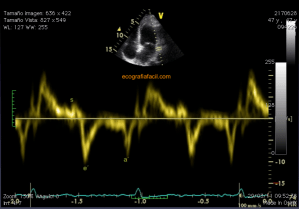

139. Ecocardiografía. Estudio Paraesternal Eje Largo.